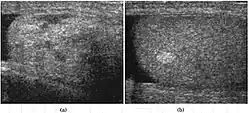

Fig. 3. Seminoma. (a) Seminoma usually presents as a homogeneous hypoechoic nodule confined within the tunica albuginea. (b) Sonography shows a large heterogeneous mass occupying nearly the whole testis but still confined within the tunica albuginea, it is rare for seminoma to invade to peritesticular structures.

Seminoma is the most common tumor type in cryptorchid testes. The risk of developing a seminoma is increased in patients with cryptorchidism, even after orchiopexy. There is an increased incidence of malignancy developing in the contralateral testis too, hence sonography is sometimes used to screen for an occult tumor in the remaining testis. On US images, seminomas are generally uniformly hypoechoic, larger tumors may be more heterogeneous [Fig. 3]. Seminomas are usually confined by the tunica albuginea and rarely extend to peritesticular structures. Lymphatic spread to retroperitoneal lymph nodes and hematogenous metastases to lung, brain, or both are evident in about 25% of patients at the time of presentation.